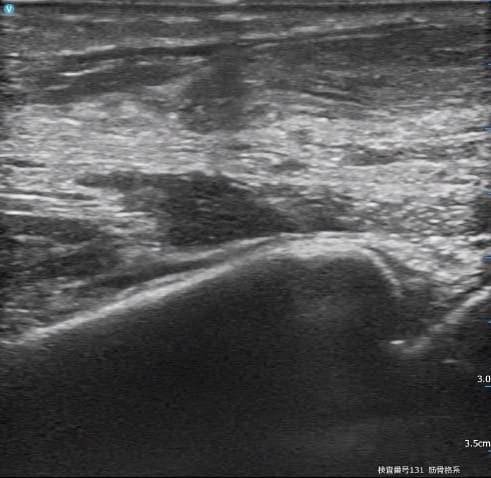

【患側:超音波エコー画像】

※繊維が黒色で消えている箇所が断裂部分です

整形外科でも超音波エコー検査を行った結果【アキレス腱断裂】と診断されました。